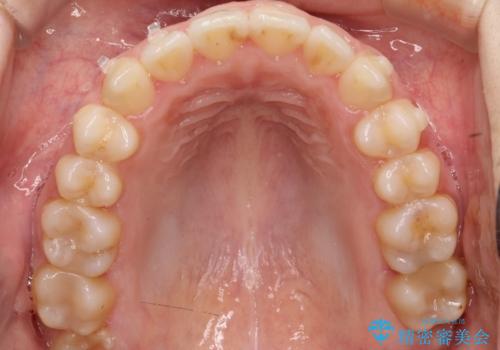

前歯のガタツキ、前歯の噛み合わせ(開咬)をインビザライン治療で治しました

- 前歯のがたつき、噛み合わせが気になるとのことで来院された患者様です。

インビザラインを使用して治療しました。

前歯がしっかり噛んでない状態(開咬)を治すために、前歯にゴムをかける必要があります。ゴムかけは患者様にご協力していただきます。